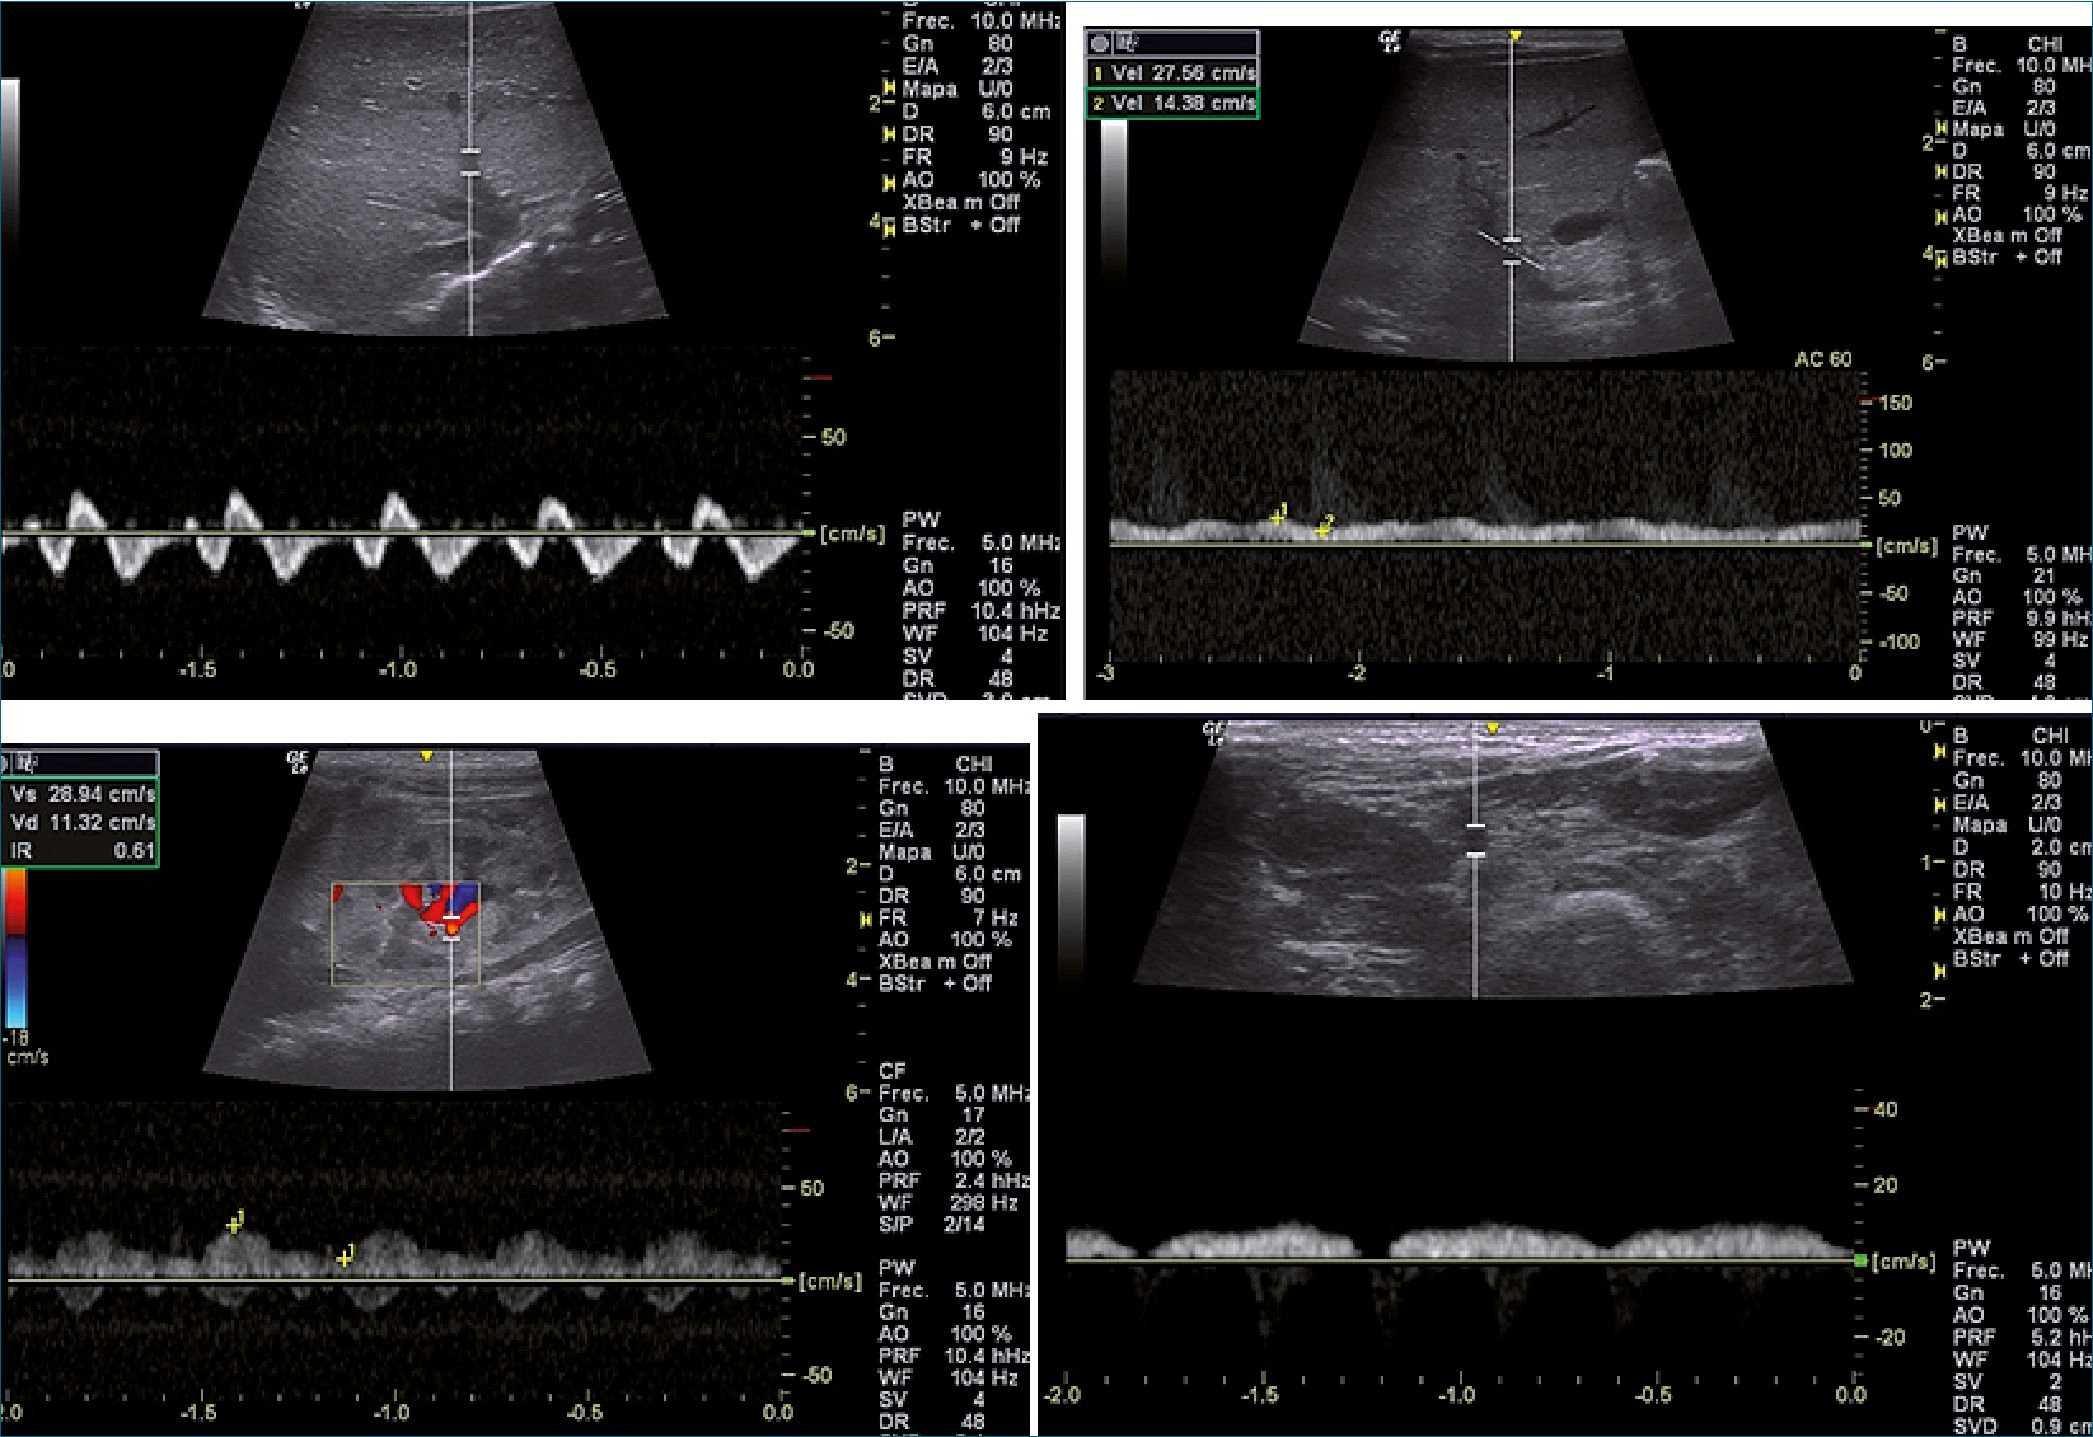

Al 7° día: el ecocardiograma muestra: dilatación de cavidades derechas con disfunción VD: TAPSE 7 mm, hipertensión pulmonar leve, PASP: 40 mmHg. El VI no está dilatado y con función sistólica normal. FAVI: 31%, se suspende soporte ino- trópico. Derrame pericárdico leve de 5 mm. Persiste, aunque en menor grado, la alteración del flujo de las venas abdominales y femorales secundaria a la disfunción del VD (Figura 3 A-B-C-D).

Figura 3. Flujos venosos después de 7 días de tratamiento. A: Flujo de la vena suprahepática, Trifásica con onda S > D y onda A persiste acentuada; B: Flujo de la vena porta, Pulsatilidad inferior: IP < 30%; C: Venas y arteria renal, vena renal pulsátil bifásica IRR: 0,61; D: Flujo de la vena femoral común, vena femoral con pulsatilidad disminuida.

En la evolución notamos la mejoría de los patrones espectrales inicialmente en los territorios venosos más distales, pero la normalización de todos los flujos solo fue evidente a las 2 semanas.